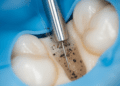

Nos casos mais avançados, a odontologia restauradora oferece opções como resinas compostas, facetas, coroas e outras restaurações que protegem o dente, recuperando forma e função. A escolha do material e técnica depende da extensão da erosão, da localização dos dentes afetados, da estética e da função mastigatória.